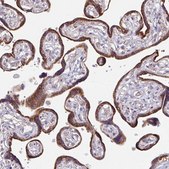

immunohistochemistry

immunohistochemistry: 1:50-1:200

The Human Protein Atlas project can be subdivided into three efforts: Human Tissue Atlas, Cancer Atlas, and Human Cell Atlas. The antibodies that have been generated in support of the Tissue and Cancer Atlas projects have been tested by immunohistochemistry against hundreds of normal and disease tissues and through the recent efforts of the Human Cell Atlas project, many have been characterized by immunofluorescence to map the human proteome not only at the tissue level but now at the subcellular level. These images and the collection of this vast data set can be viewed on the Human Protein Atlas (HPA) site by clicking on the Image Gallery link. We also provide Prestige Antibodies® protocols and other useful information.

- IHC tissue array of 44 normal human tissues and 20 of the most common cancer type tissues.